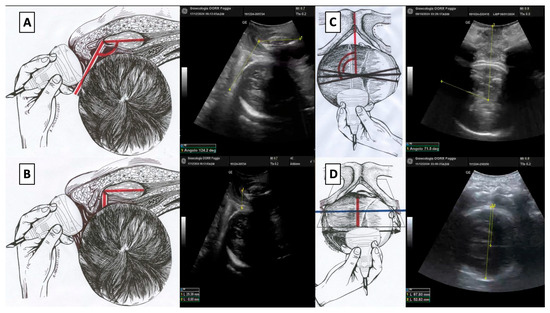

2.2. Ultrasound Assessment and Parameter Measurement